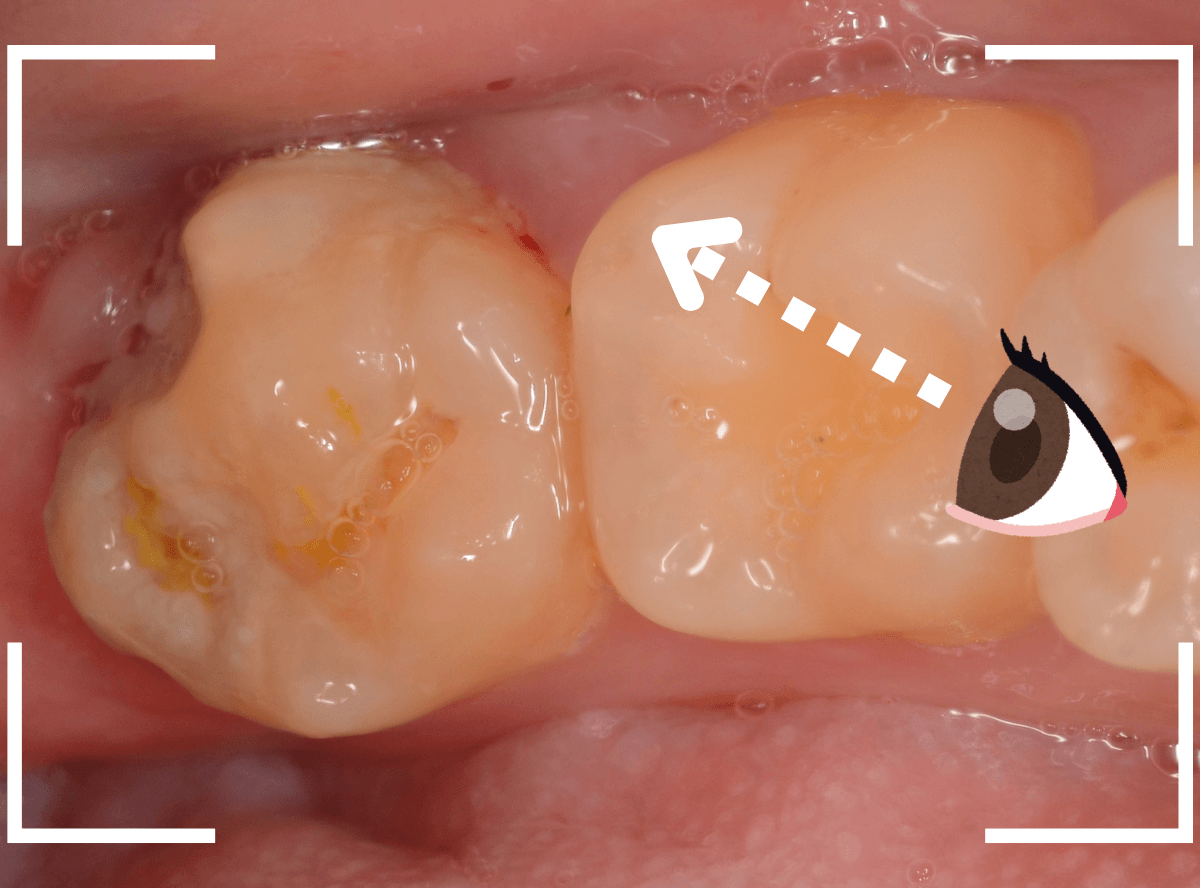

このようなおやしらず、あなたはありませんか?